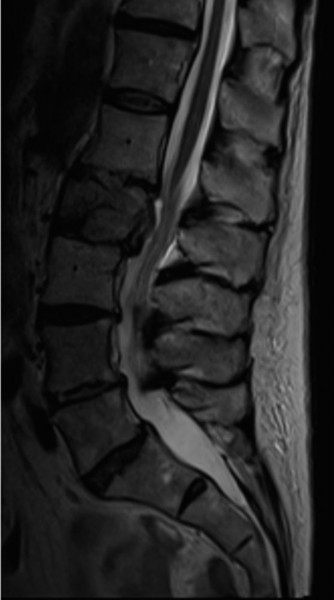

CASE 11 A 45-year-old man is brought to the trauma bay after falling from his r…